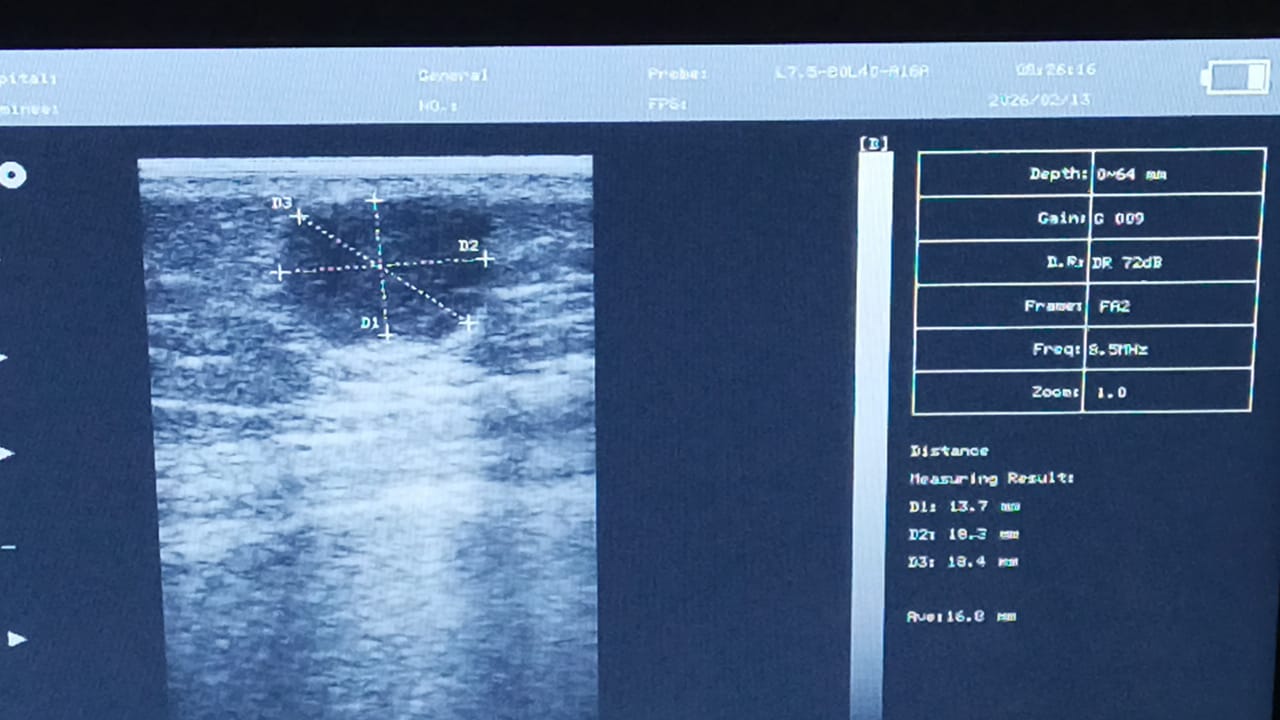

Paciente acude a consulta de cirugía menor para la exéresis de una lesión nodular ubicada en la región lateral del tercio proximal del brazo izquierdo.

Previo a la intervención, se realizó un rastreo ecográfico para evaluar la profundidad y extensión de la lesión. El especialista a cargo reportó: "La imagen ecográfica, previa a la cirugía menor, fue EXCELENTE. Con gran nivel de nitidez. Gracias." La resolución de la imagen permitió delimitar perfectamente los bordes del quiste facilitando un abordaje quirúrgico seguro.

Ecógrafo Portátil B/N CMS600P2